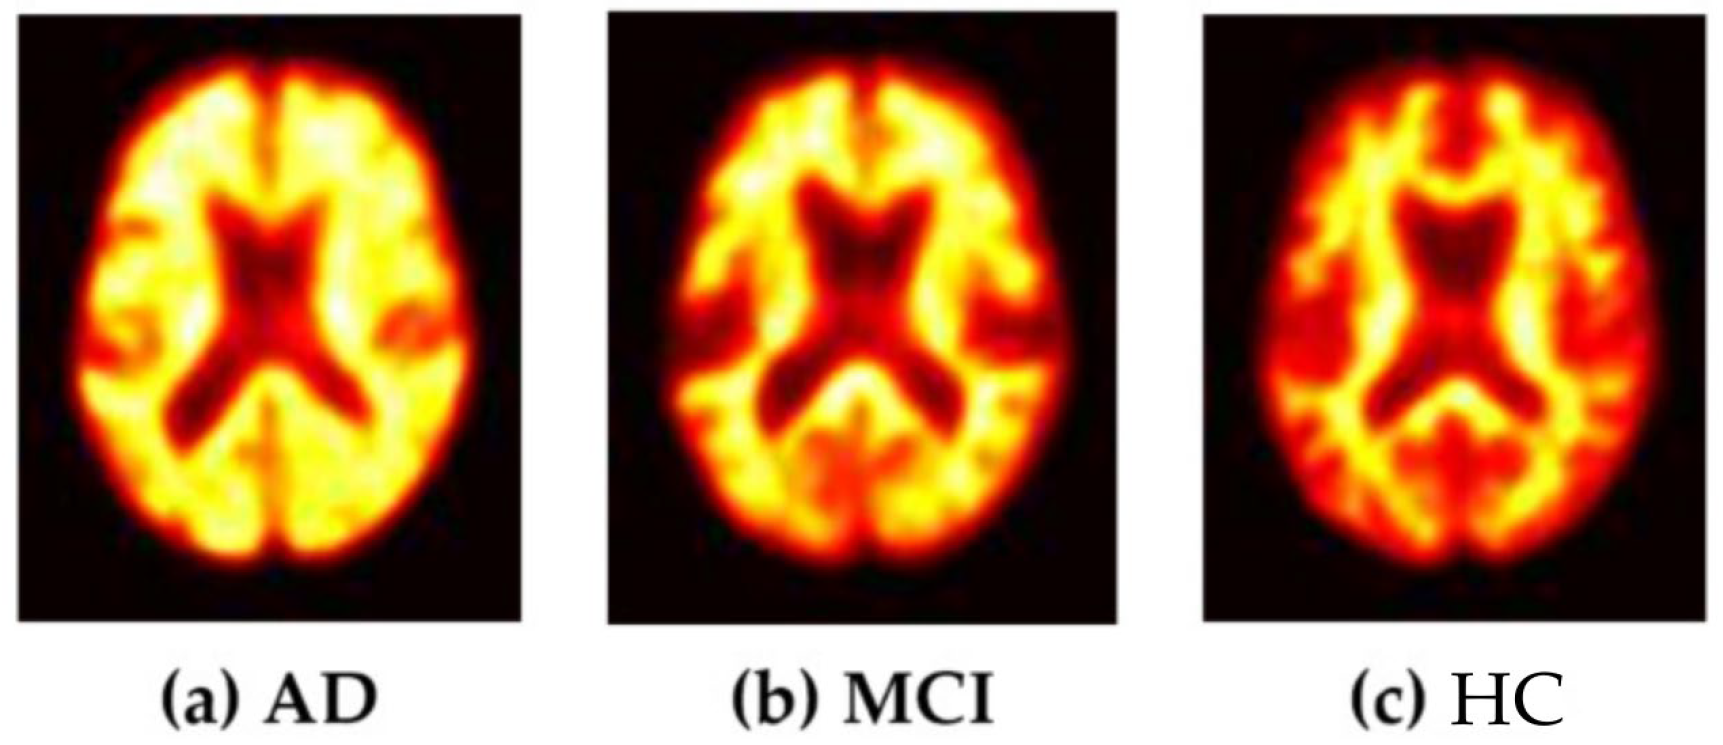

This study included subjects with dual FBB images who underwent FBB testing between 1 April 2016, and 30 June 2022, in the Dong-A University cohort. In total, 716 subjects underwent FBB testing during this period. We included 383 subjects, excluding those with neurological, medical, or psychiatric disorders, as well as cases of unavailable or damaged images. The 383 subjects were classified according to their diagnoses into 220 patients with AD, 113 patients with MCI, and 37 subjects as HC (Table 1, Figure 1). Each phase of an FBB image was confirmed by a nuclear medicine physician following collection to ensure that the Aβ distribution labels were accurate. The brain amyloid plaque load (BAPL) score is a system measured by a doctor according to the visual assessment of amyloid deposition. BAPL is a three-grade scoring system: BAPL score 1 is No Amyloid-β Load, BAPL score 2 is Minor Amyloid-β Load, and BAPL score 3 is significant amyloid-β load [35]. During binary classification, subjects with AD and MCI were classified in the “abnormal group,” whereas HC subjects were classified into the “normal group”. The Dong-A University Hospital Institutional Review Board (DAUHIRB) reviewed this study with the members who participated in the Institutional Review Board Membership List and approved this study protocol (DAUHIRB-17–108).

Figure 1.

Preprocessed FBB images of subjects. (a) FBB image of AD. (b) FBB image of MCI. (c) FBB image of HC.